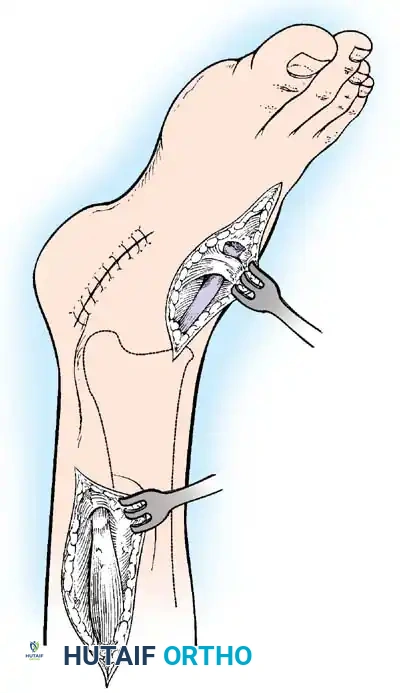

Paralytic Calcaneus:

A devastating deformity resulting from triceps surae paralysis. The unopposed dorsiflexors pull the foot into calcaneus, while the intrinsic muscles and plantar fascia contract, creating a calcaneocavus deformity. Reconstruction requires plantar fascia release, followed by transfer of the tibialis posterior, peroneus longus, and flexor hallucis longus to the os calcis to restore plantarflexion power.